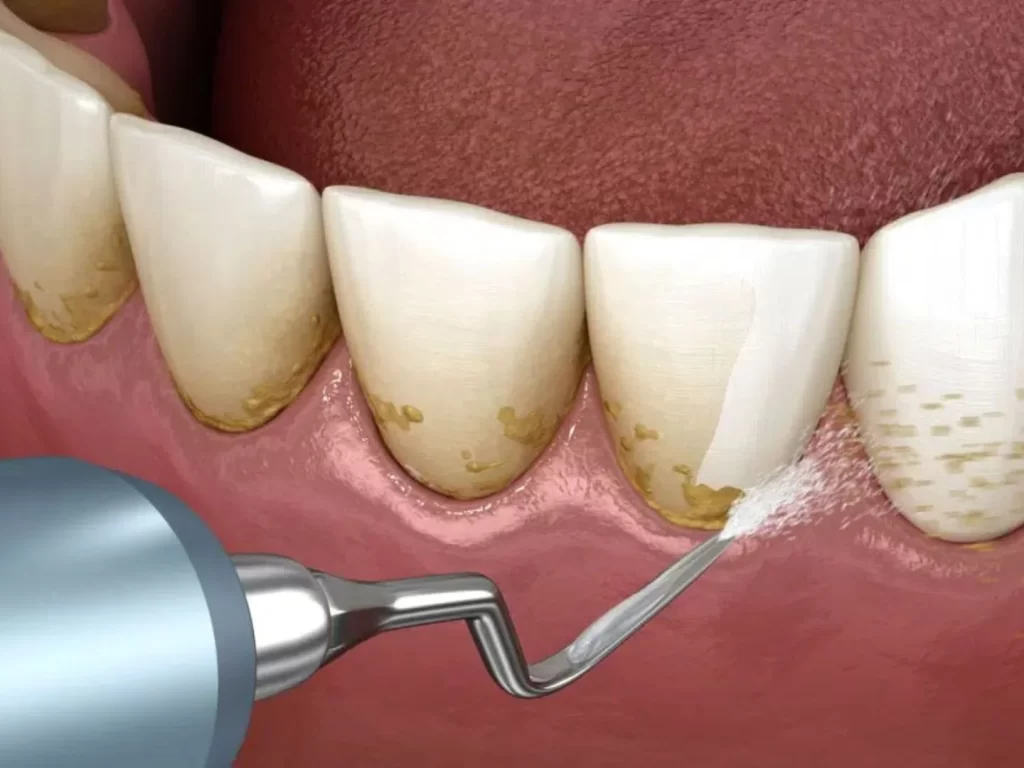

2. Raspagem supragengival

Com instrumentos manuais (curetas) ou ultrassônicos (aparelhos que vibram), o profissional remove mecanicamente o tártaro visível acima da gengiva.